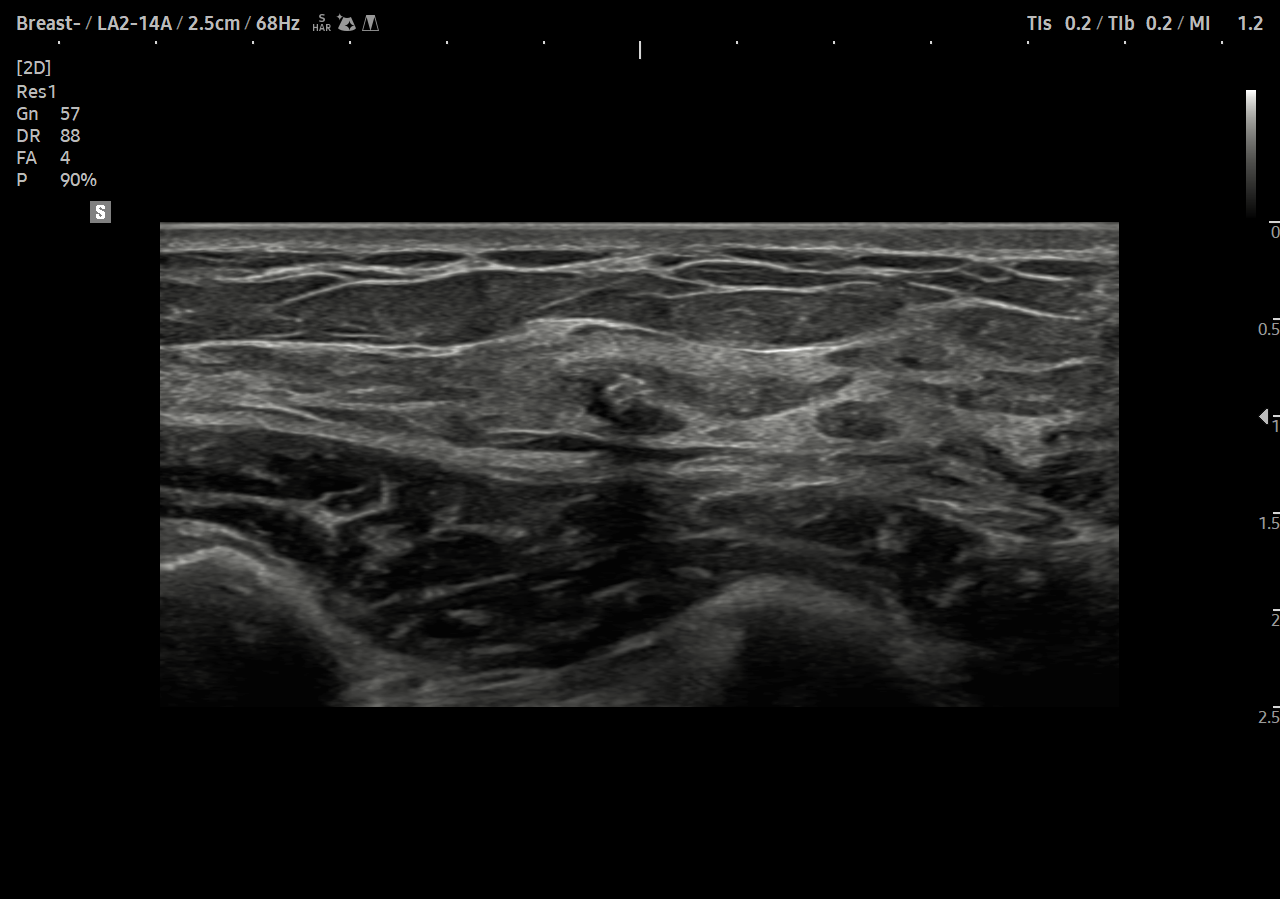

S-Detect for Breast analizează leziunile detectate în timpul examinării ecografice a sâni și afișați datele de analiză, aplicați BI-RADS ATLAS * (Breast Imaging- Reporting and a Data System, Atlas) pentru a furniza raportări standardizate și pentru a oferi suport de diagnostic cu un flux de lucru simplificat